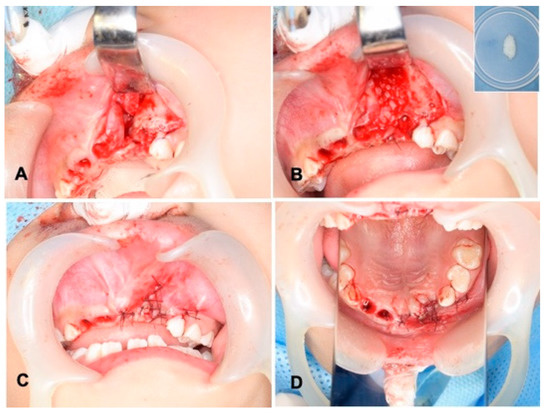

2.4. Surgical Procedure of Unilateral Alveolar Cleft and Autograft of DDM

Gross View and Radiographic Evaluation after Surgery